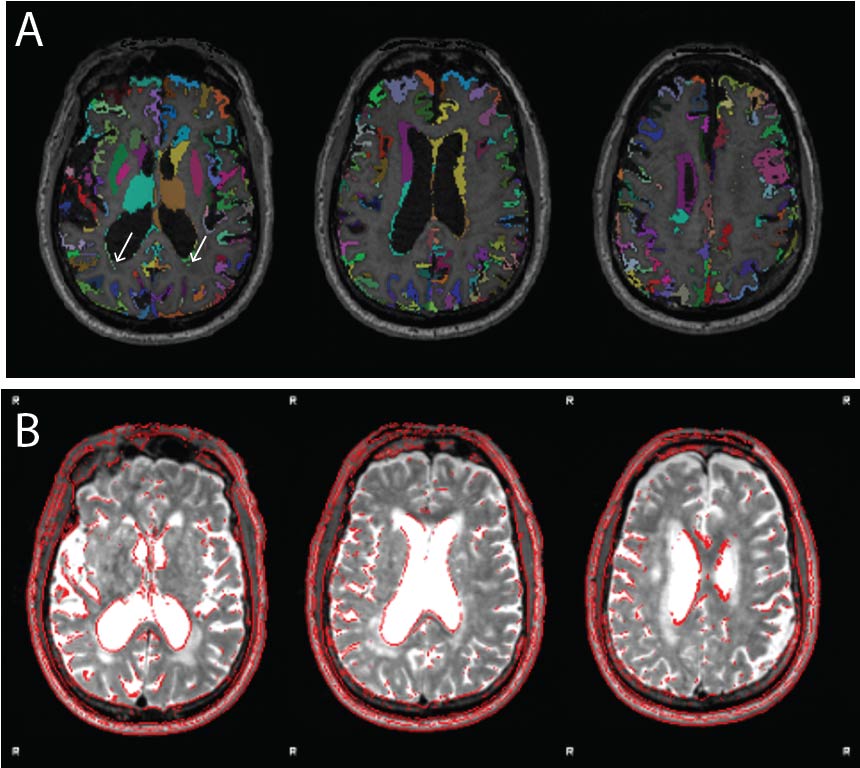

The labelled and unlabelled segmentation outputs are also examined, and the accuracy of tissue classification (especially the delineation of grey and white matter) is assessed. Misclassification of non-brain tissue (i.e., inclusion in grey and white matter segmentations) is also noted. For older adults in the Cam-CAN sample (≥50 years), we also checked if white matter lesions were misclassified as grey matter during segmentation. This was supported by also inspecting the T2* image in conjunction with the T1w. Figure 7 shows an example of white matter lesions being classified as grey matter. In cases with high WML loads, this will be impossible to avoid, and QC involves deciding to what extent the misclassification impacts tractography, namely the placement of seed and target ROIs, which will be covered below. Finally, the registrations of the structural images to the MNI template are also inspected. Poor brain extraction and/or significant brain atrophy can affect the quality of the registration. Since the parcellation is defined on the MNI template, poor registrations can substantially hinder the parcellated downstream outputs from both the functional and diffusion sub-pipelines. Similar procedures are followed for examining T2* images. For T2 FLAIR images, like those in the ADNI3 dataset, lesion classification outputs from BIANCA are also examined.

Figure 7. Example of white matter lesion misclassification as grey matter. (A) The labelled grey matter image is shown on the T1w. (B) T2* image from the same older adult subject indicating a significant volume of white matter lesions that are also notable on the T1w. Although performing segmentation on the T1w image using age-specific tissue priors is largely successful despite the large white matter lesion volume, some misclassification remains (white arrows in panel A). Images reproduced from the example subject’s QC report.